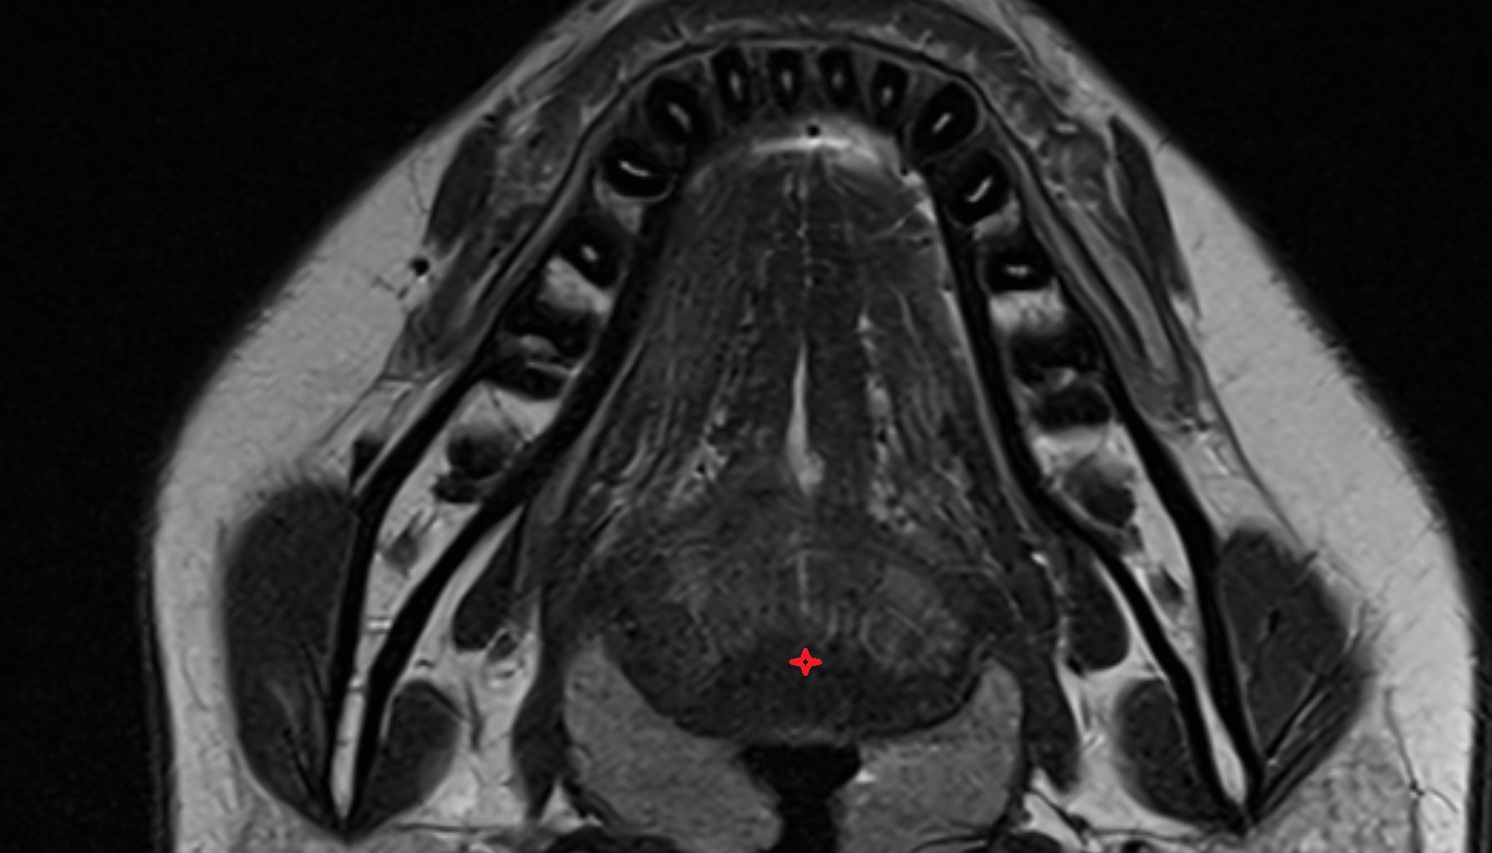

- Temporomandibular joint

- Mandibular condyle

- Mandibular fossa

- Articular disc of temporomandibular joint

- Articular eminence

- Articular surface of mandibular fossa

- Mandible

- Lateral pterygoid muscle

- Masseter muscle

- Medial pterygoid muscle

- Temporalis muscle